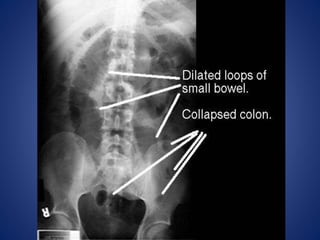

RADIOLOGICAL PICTURE

 Small Bowel Obstruction

- Central distention (GAS)

- Valvulae conniventes

- “Ladder-like dilatation”

- Small diameter

 Large Bowel Obstruction

- Peripheral distention “Picture frame”

- More gross distention

- Haustral indentation & large diameter

In most cases, the abdominal

radiograph will have the

following features:

1. ileated loops of small

bowel proximal to the

obstruction

2. predominantly central

dilated loops

3. dilatation of loops over

3cm

4. valvulae conniventes are

visible

Large Bowel Obstruction